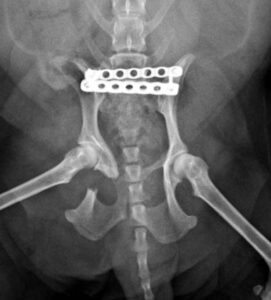

13歳のマルチーズちゃんが骨盤骨折で来院されました。ロッキングプレートを使用した仙腸関節安定化術(TAITAN1.7と1.5)で固定する手術を行いました。術後元気に歩けるようになりました。よかったね。